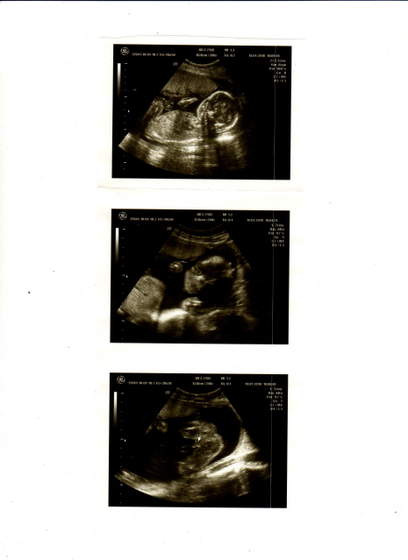

Nasze fasolki na USG

witam pokaże Wam moją córeczkę - jeśli mi się uda :baffled: